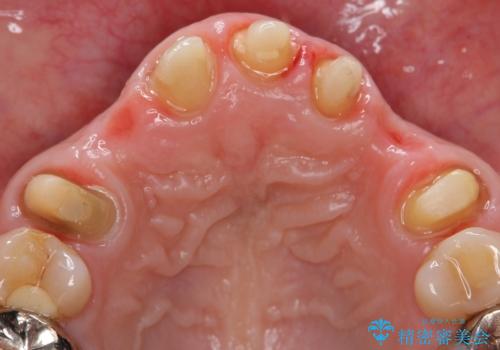

- 昔治療した前歯の被せ物の見た目を改善したいといらっしゃった方の症例です。

左上4番目の歯から右上3番目の歯まで計7歯のクラウンを除去し、オールセラミッククラウンによる補綴を行いました。